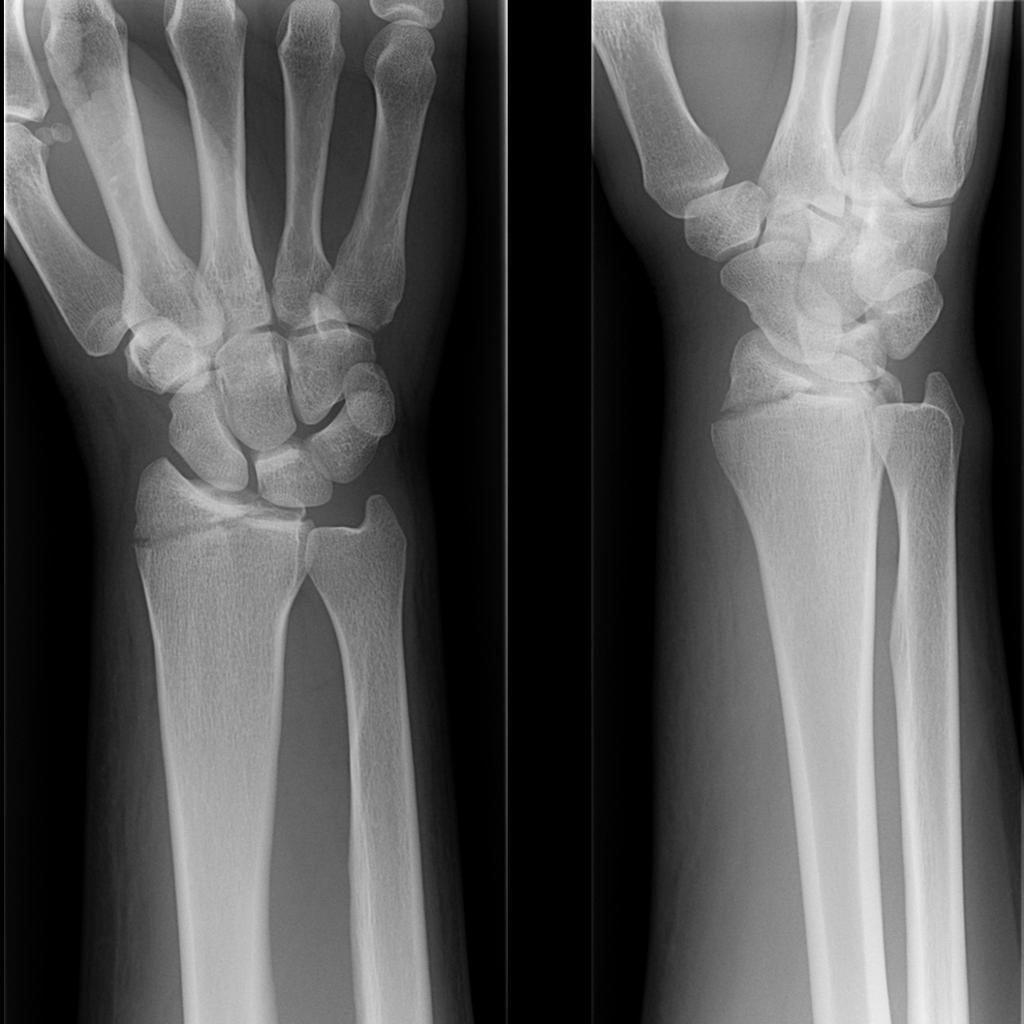

This page is about smith fracture contains smith fracture smith fracture smith fracture smith fracture